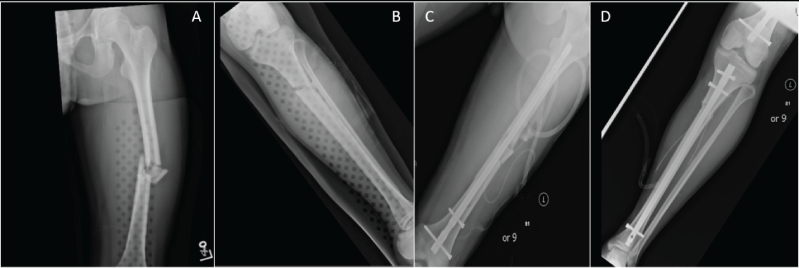

19 year old male was admitted to a tertiary trauma center after a motor vehicle accident. The mechanism involved a head-on impact by the patient's vehicle into a dump truck. After full trauma screen, the injuries discovered were limited to a mid-shaft left femur and upper third left tibial fractures. The head CT was negative (Figure 1).

Figure 1: Initial fractures of the left femur and left tibia are shown in (A) and (B). Post- operative films with intra-medullary rods transfixing both fractures are shown in (C) and (D).

At time of admission the patient was fully oriented, conversant, breathing spontaneously with normal laboratory values except first measured platelet count of 80 K. He was taken quickly to the operating room for placement of intra-medullary rods in the left femur and left tibia. Post operatively he was agitated, disoriented, hemodynamically unstable, tachycardic and ventilator dependent. CT of the chest was negative for bland pulmonary emboli but revealed scattered patchy parenchymal infiltrates. Platelet count reached a nadir of 67 K then rebounded rapidly as shown in figure 2.

28 year old female driving a motor vehicle, opposite to the normal flow of traffic on a major city circumferential highway and at extremely high rate of speed, collided head on with an 18 wheel tractor-trailer. Sustained injuries included atlanto-occipital dissociation (AOD), severe laceration/maceration of the right lobe of the liver, bilateral femur fractures (right femur mid shaft, left femur mid shaft and subtrochanteric), left tibia and fibula, left ulnar fracture (Figure 4).

Figure 4: Initial injuries in patient #2 with right mid-shaft femur (Image A), leftmid-shaft femur and sub-trochanteric fracture (image B), and left tibial mid shaft fracture (image C).